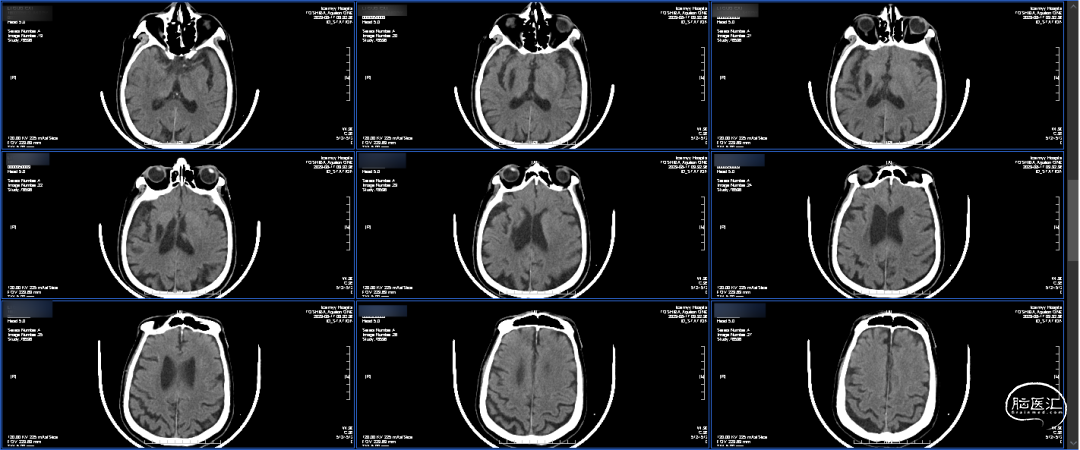

术前CTA:双侧颈内动脉闭塞,代偿可。

术前CTA:颅内代偿可。

CTP:左侧大脑半球大面积TTP及MTT延长,CBV左侧大脑半球大面积TTP及MTT延长,rCBV基本正常或轻度下降,rCBF下降,符合脑梗死前期Ⅱ1期表现。